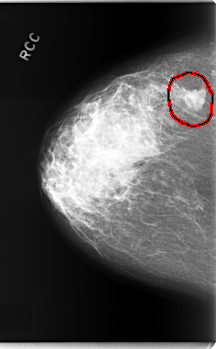

FILE: C_0208_1.RIGHT_CC.OVERLAY

TOTAL_ABNORMALITIES 1

ABNORMALITY 1

LESION_TYPE MASS SHAPE IRREGULAR MARGINS MICROLOBULATED

ASSESSMENT 5

SUBTLETY 5

PATHOLOGY MALIGNANT

TOTAL_OUTLINES 1

BOUNDARY